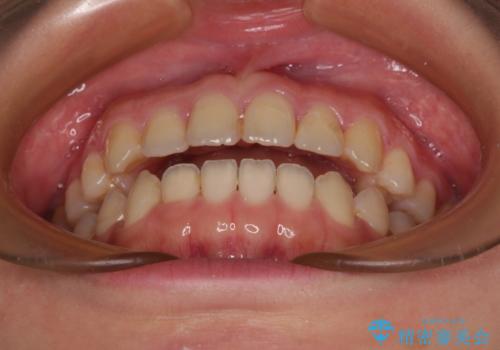

前歯のオープンバイト インビザラインで咬み合わせを改善

- 前歯の開咬を気にして来院された患者様です。

開咬の治療は、前歯を閉じるように動かすとともに、上下臼歯を圧下(骨内にめり込ませる)させることで進めて行きます。

インビザラインは臼歯の圧下を効果的に行えるため、インビザラインを用いて矯正治療を行うこととしました。